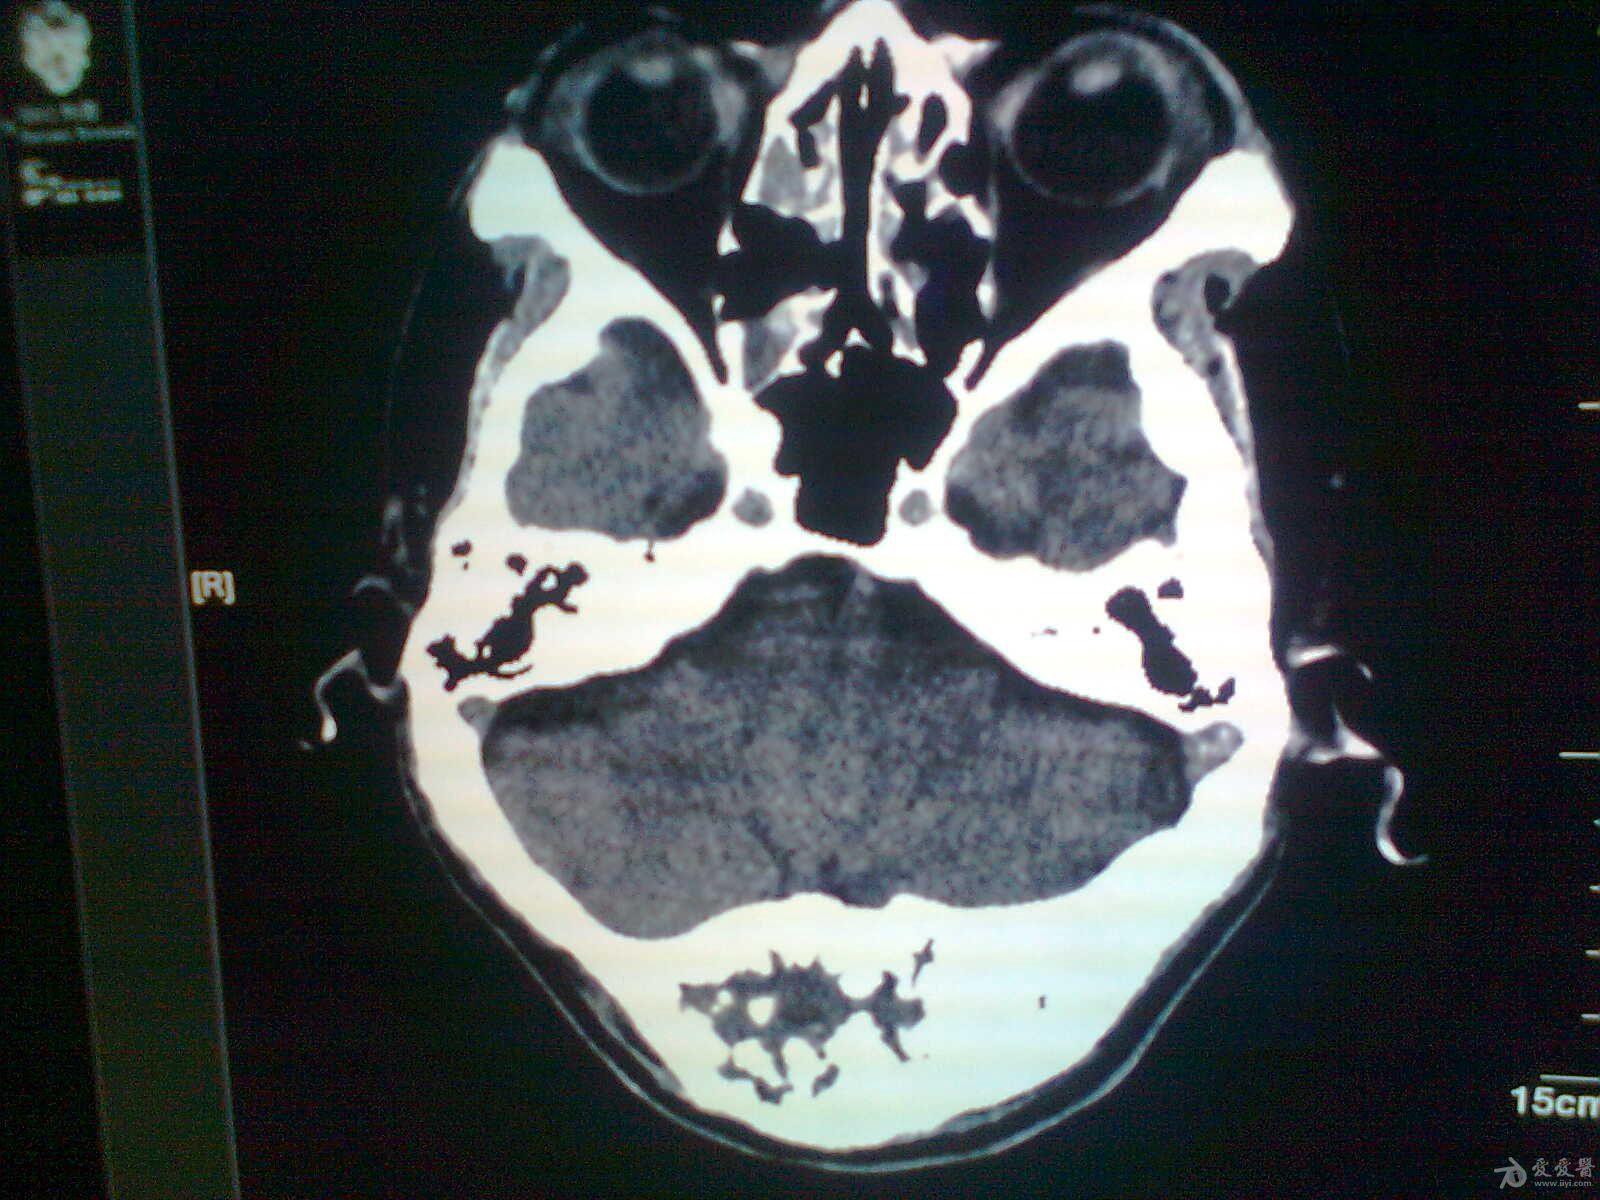

医生是怎么根据这张ct来分析我的骨瘤的?

图片尺寸1080x1440